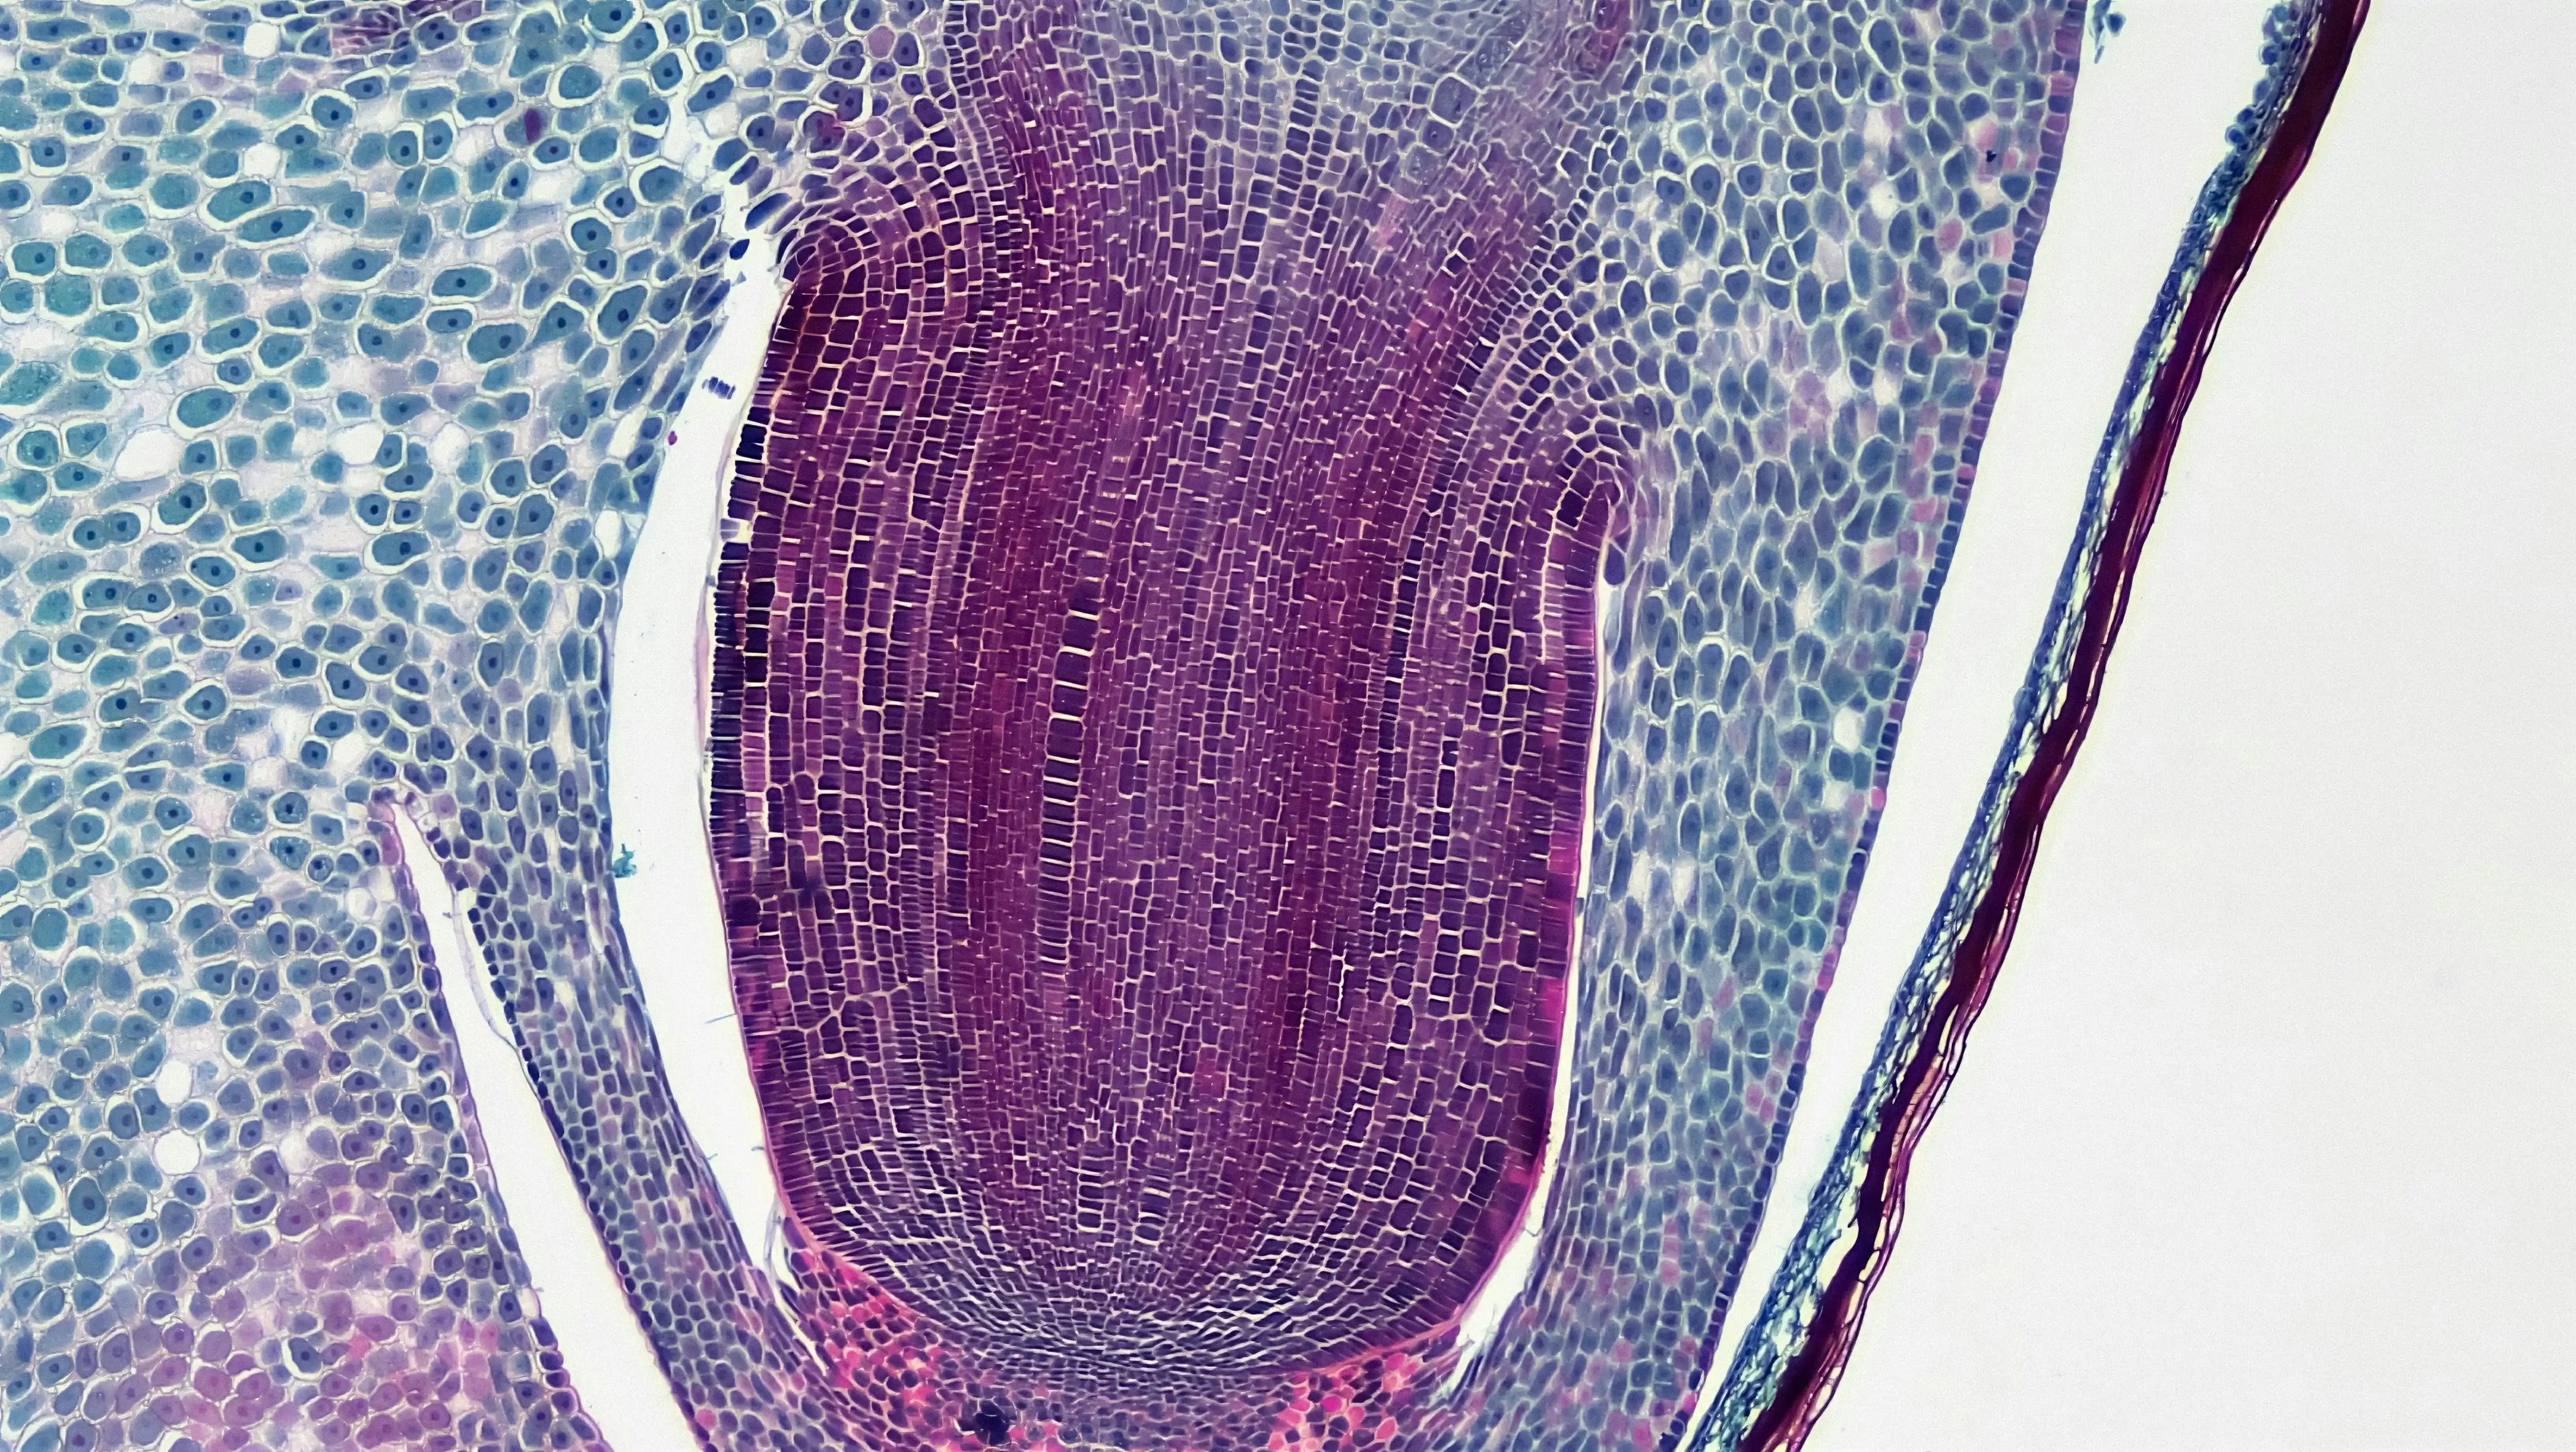

혈뇨는 그 양상에 따라 육안으로 보이는 육안적 혈뇨와, 현미경으로만 발견되는 미세혈뇨로 나뉩니다. 각각의 형태는 다양한 혈뇨 원인을 시사하며, 그에 따라 대응 방식도 달라집니다.

- 미세혈뇨: 사구체신염, IgA 신증, 신장기능 저하 등 보다 깊은 내과적 질환과 연관이 있습니다.